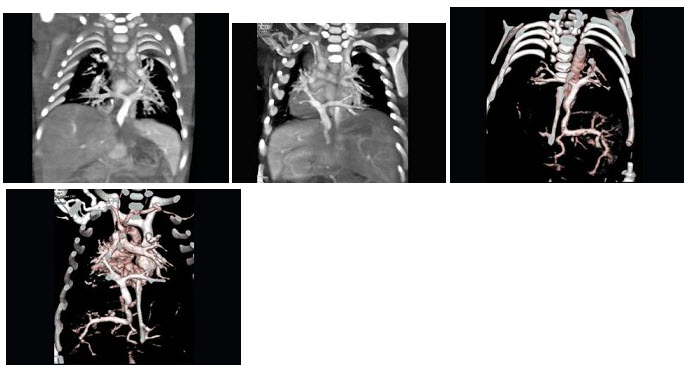

104、多项选择题

女,21岁,活动后呼吸困难,CT扫描如图,最可能的诊断是()

A.肺静脉异位引流

B.肺静脉异位引流根据引流肺静脉支数可分部分性及完全性

C.根据引流部位不同分为心上型、心脏型、心下型

D.该病例肺静脉异位引流入下腔静脉

E.该病例为心下型肺静脉异位引流